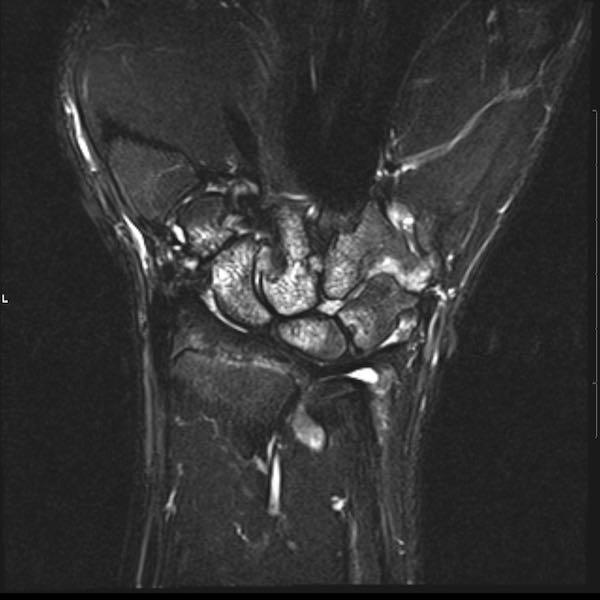

Tiếp tục xem hình ảnh MRI của bệnh nhân này.

Hình ảnh MRI:

Tràn dịch lan tỏa tất cả các khớp cổ tay.

Phù tủy xương lan tỏa tất cả các xương cổ tay.

Bào mòn xương, ví dụ tại xương thuyền, xương đầu và xương móc.

Phá hủy khe khớp và sụn khớp, rõ nhất tại khớp STT và CMC4/5.